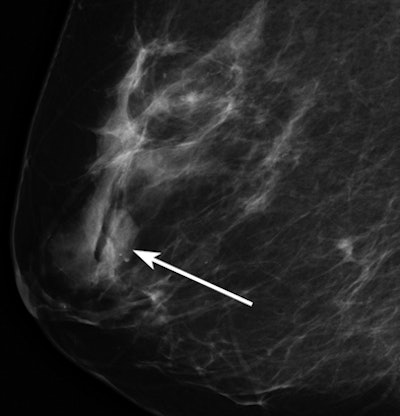

| Mammographic image of a low-density mass (arrow). All images courtesy of the Radiological Society of North America. |